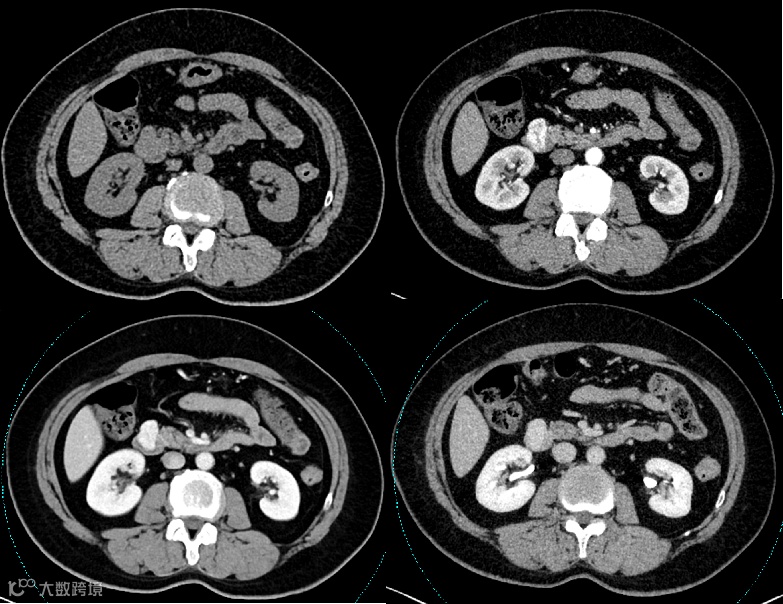

女性,77岁

主诉:上腹烧灼感1周余

现病史:患者近1周余偶有上腹烧灼感,偶有反酸,大便 2-3 次/日,成形色黄

胃镜检查:1.球降交界处粘膜隆起(性质待查) 2.胃体隆起(外压?) 3. 慢性胃炎急性活动

既往史:2019年于我院因结节性甲状腺肿行手术治疗,术后口服优甲乐,恢复可;2020-03-17在全麻下行右侧保留乳房的乳腺癌切除术,术后病理:浸润性癌病理分期:ⅡA(T2,sN0,M0)

影像学表现